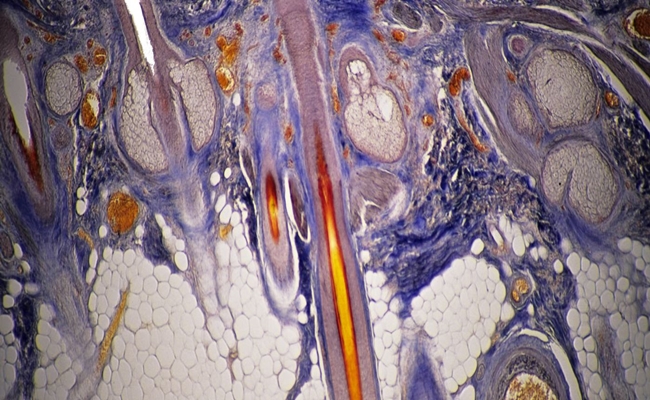

و أثناء دراسة الصلع وبصيلات الشعر، اكتشف تشوي كانج-يول في جامعة يونسي في العاصمة الكورية الجنوبية سول وفريقه وجود كمية كبيرة من بروتين “سي إكس إكس سي5” في فروة رأس المصابين بالصلع، ووجد الباحثون أن ارتباط هذا البروتين مع بروتين ديشيفيلد يمنع تجدد بصيلات الشعر.

أنتج الفريق مادة “بي تي دي-دي إم بي” كي يمنع هذا الارتباط.

واختبر الفريق مادة “بي تي دي-دي إم بي” على الفئران فلاحظ نمو بصيلات الشعر مجددًا بعد استخدام هذه المادة لمدة 28 يومًا، ويختبرها الفريق حاليًا على حيوانات أخرى كي يحدد مستوى سميتها. وإذا أسفرت هذه الاختبارات عن نتائج إيجابية فستكون الخطوة التالية هي البدء في تطوير دواء وتجريبه على البشر.